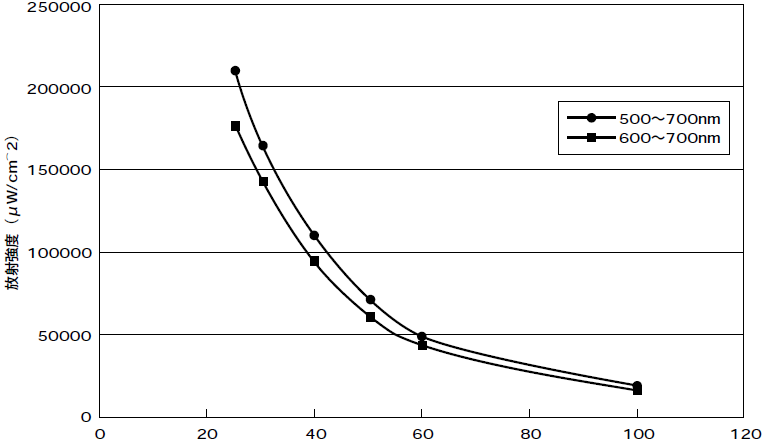

レンズヘッド全面からの距離と放射強度

レンズヘッド全面からの距離(mm)